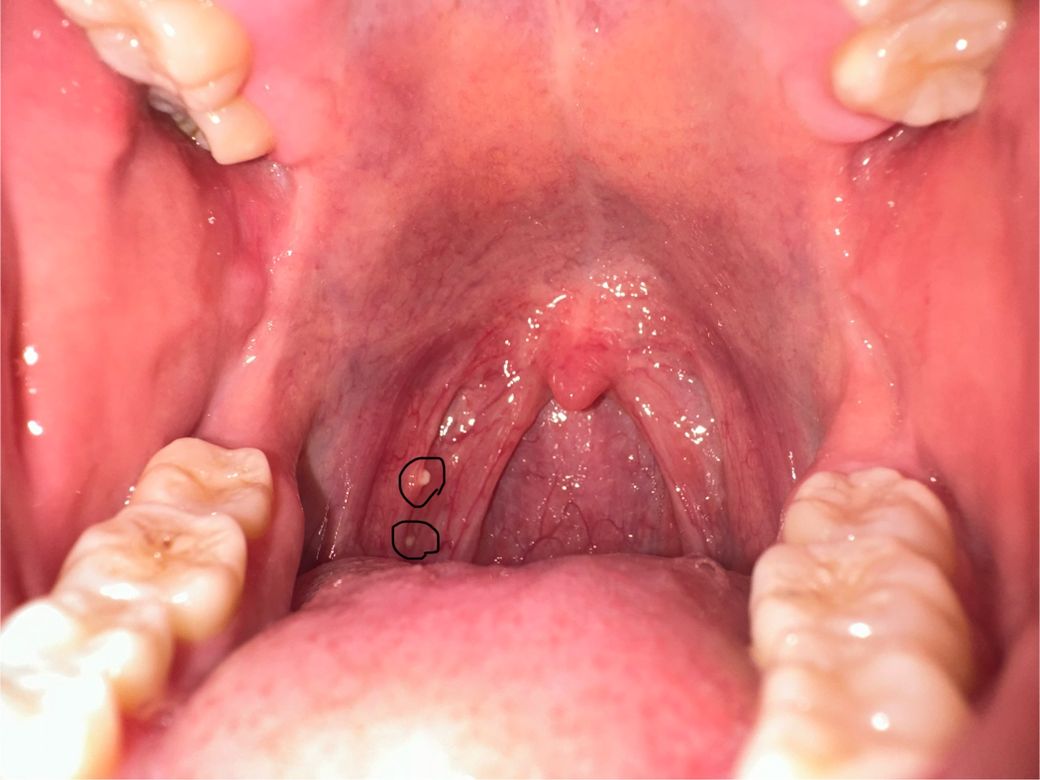

이틀전 아침부터 이물감이 들길래 물도 많이 먹어봐도 이물감이 그대로더라구요ㅠ 그리고나서 신경도 안쓰고 있다가 빛비춰보니 저런 알갱이같은게 있는데 인터넷 쳐보니 편도 결석이라는데 맞나요? 양치랑 관련이 있는지, 아프진 않은데 제거를 해야하는지 방치해도 되는지 궁금합니다 이물감은 여전해요ㅠ

• 1번 째 사진